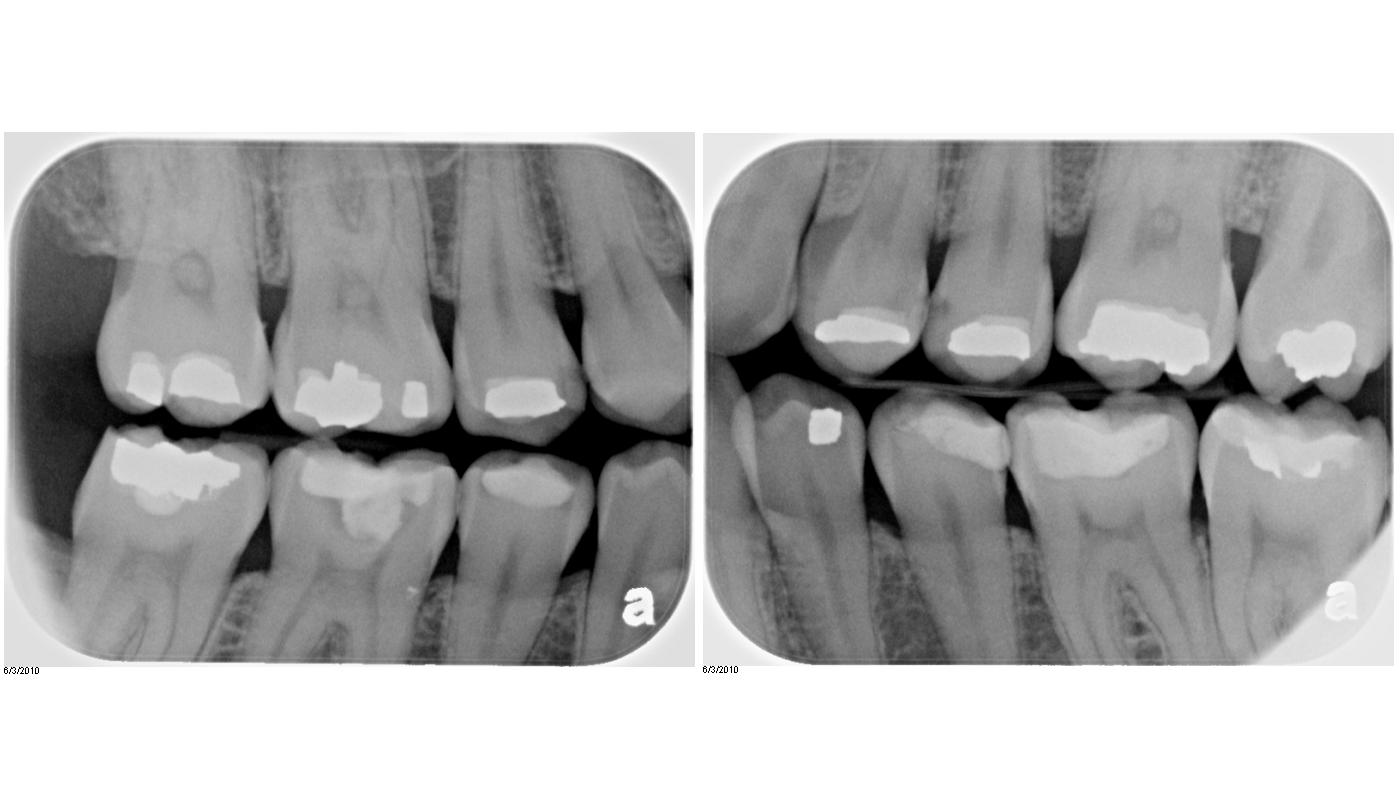

Dental News and Views Initial Dental Exam

Dental News and Views Initial Dental Exam Dental Code For Bitewings The aim of this review was to identify guidelines on when and how frequently bitewing radiographs should be used in dentistry for the. D0210 is typically paid once every three to five years. Bitewings are a type of dental radiograph that. In addition, we included the following codes for dental examinations in the analyses of the radiographic imaging codes: Although. Dental Code For Bitewings.